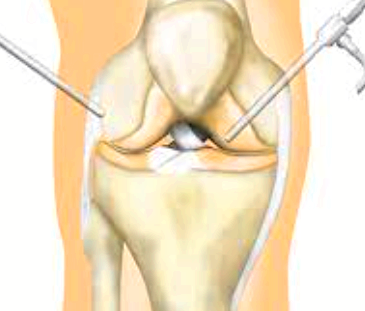

주사요법으로도 치료가 어려운 경우에는 관절내시경 수술을 통해 연골을 재생시키는 방법이 있습니다. 이를 연골 입자 이식술이라고 하는데요. 원래의 연골 중 일부를 떼어내서 이를 손상부에 주입함으로써 연골을 재생하는 방법입니다.

이 방법은 기존 방법과는 달리 재생되는 연골이 원래의 연골 성질과 내구성이 비슷한 연골로 재생이 되므로 이후에 퇴행성 관절염을 예방하는데 효과가 있습니다. 연골이 스스로 재생되지 않기 때문에 인위적인 방법으로 재생을 해주어야 합니다. 이 방법 역시 완전한 재생은 어렵기 때문에 평소 무릎을 사용할 때 주의하시는 것이 중요합니다.